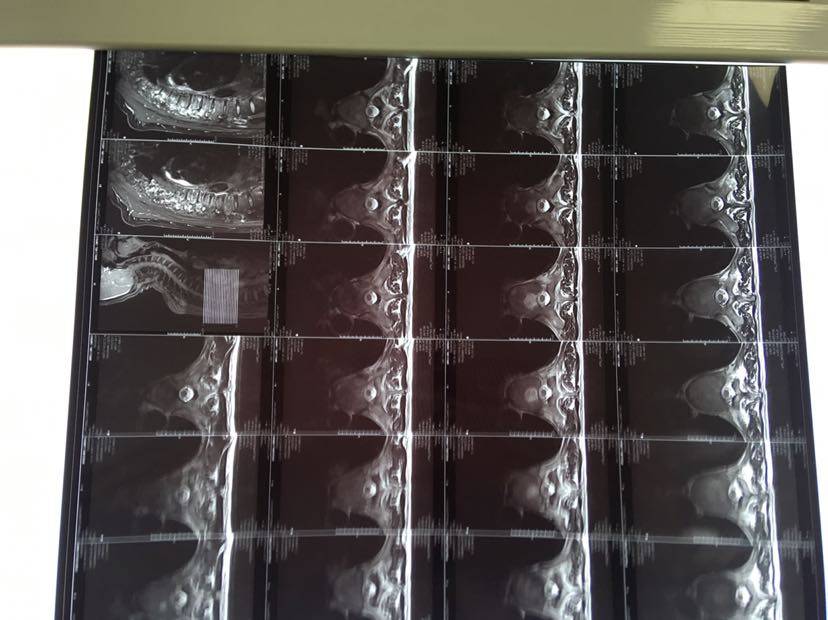

爸爸吃易瑞沙8个月,各项血常规,肝肾功能都在正常范围内,肿标不敏感,一直都在正常范围内,肿瘤现在维持大小不变,每个月一阵骨转移,打了五个月了,当时发现的时候一直没有做骨扫描,也不知道具体骨转程度,这次做了脑部赠强核磁,颈椎,胸椎,腰椎核磁,结果颈椎,胸椎多发转移瘤,家里县城的医生说没有办法,接着吃靶向药就可以了,去济南齐鲁医院医生说先吃靶向药,打骨转移吧,我感觉颈椎很危险,不知道怎么办,广州这边医院还在挂号中,请问各位有没有类似的情况,怎么处理的,放疗的话副作用是不是特别大

陈医生这是每个月肿标